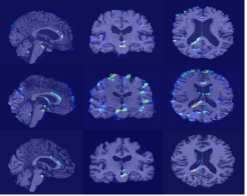

Refer to caption

(a) 3D U-Net

(b) EFDM

(c) EM1

(d) EM2

Figure 4: t-SNE visualizations of sMRI embeddings under different training settings. Data were drawn from four cohorts: NACC, ADNI, AIBL, and OASIS. The vanilla 3D U-Net (a) shows clear cohort-specific clustering, with AIBL forming compact islands and OASIS concentrated in the upper region, while ADNI and NACC remain distinct. EFDM (b) increases inter-cohort mixing, creating a dense shared embedding space though NACC still trends toward the outer edge. EM1 (c) and EM2 (d) further enhance overlap, dispersing cohort-specific clusters and producing a more uniform interleaved structure.

Lastly, across the t-SNE embeddings in Fig. 4, the vanilla 3D U-Net in Fig. 4a showed the clearest separation between cohorts, with AIBL forming several islands and OASIS concentrated in the upper region. EFDM in Fig. 4b produced slightly better inter-cohort mixing, although NACC showed clustering toward the outer edge. EM1 in Fig. 4c further dispersed cohort-specific islands, distributing AIBL and OASIS more uniformly and increasing overlap throughout the embedding without obvious isolated clusters. EM2 in Fig. 4d shows a similar degree of mixing to EM1, with a slightly tighter interleaved core and only a few outer zones dominated by NACC. Overall, the progression from baseline to EFDM and then to EM1/EM2 illustrates a shift from dataset-driven clustering toward reduced cohort bias.